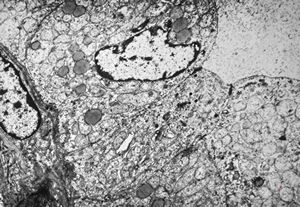

F, 71y. | carcinoid … metastasis to lymphonode